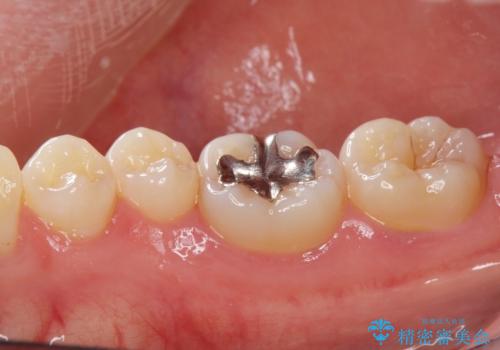

- 口を開けたとき銀歯が見えるのが嫌で白くしたいとの事で来院。

銀歯を除去してセラミックインレー(e-maxインレー)での治療となりました。

白い詰め物(e-maxインレー)にしたことにより、口を開けたとき目立たなくなりました。